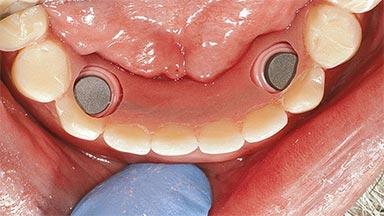

Improving an Existing Implant-supported Denture in an Alzheimer Patient with Bipolar Affective Disorder with Moderate Depression and Dementia

An 83-year-old man presented together with his caregiver at the dental department of the Medical University of Innsbruck, Austria with complaints of swelling in the right maxillary canine area and loss of retention of his 5-years-old mandibular denture. The patient had a significant medical history (20 years) of bipolar affective disorder with moderate depression (F 31.3) and dementia in Alzheimer’s disease (F 00.2). The patient had been in ambulant psychiatric therapy for his depressive illness for the past 20 years. He lived alone and had no children; his sister assisted with daily living. She reported that the patient exhibited compulsive hoarding behavior. In the previous two months, she had noted increasing disorientation and vertigo in the patient. She therefore accompanied him for a medical consultation at the Department of Psychiatry and Psychotherapy of the Medical University of Innsbruck. He was released home after a 6-week inpatient stay.

# of Implants 2

Type of Implants One-Piece

Attachment One-Piece